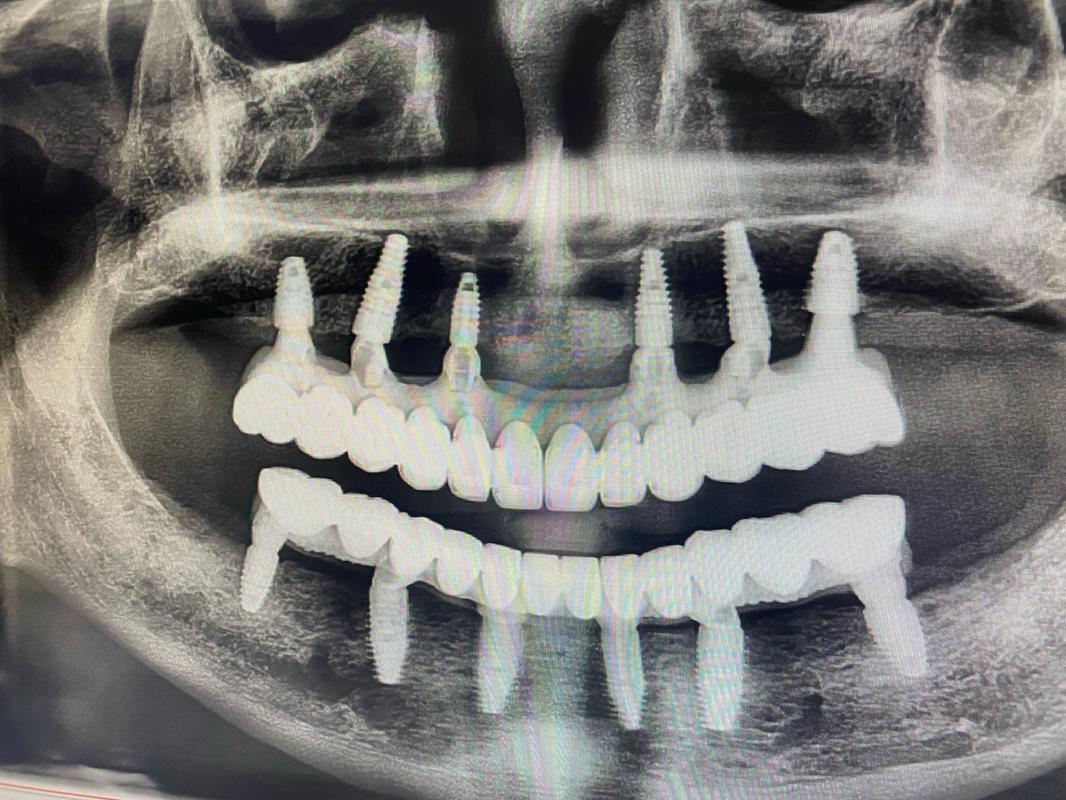

方案3:All-on-4/6半口/全口种植——“骨量不足也能半口牙重生”

针对半口/全口缺牙、牙槽骨严重萎缩的患者,传统种植可能需要大量植骨,而“All-on-4/6”技术通过“倾斜植入+即刻负重”,用4颗或6颗种植体支撑半口牙桥,避开骨量不足区域,实现“当天种牙、当天用牙”。

- All-on-4:在缺牙颌骨植入4颗种植体,其中后牙区种植体倾斜植入(避开上颌窦/下齿槽神经),利用现有骨量,戴入固定牙桥;

- All-on-6:增加2颗种植体,提供更强支撑力,适合骨量稍好或对咬合力要求高的患者。

优点:避免全口植骨,治疗周期短(1-3天),恢复咀嚼功能;缺点:对医生技术、种植体品牌要求高,费用相对较高。